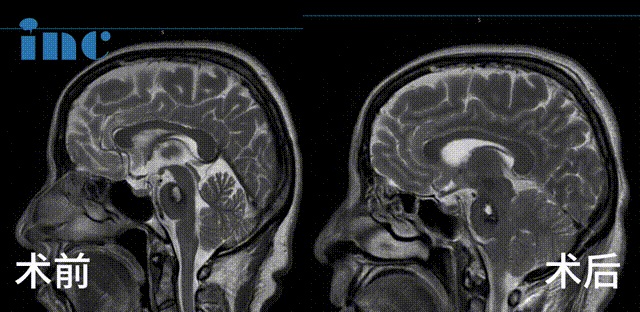

▼金女士术后3个月影像对比

2023年9月28日,巴教授于苏州大学附属独墅湖医院为金女士顺利手术,巴教授成功为金女士取出了这颗脑干位置的不定时炸弹,无任何新发神经功能损伤,同时巴教授也成功进行了面神经解压术,解决了金女士面肌痉挛的问题。

▼术前及术后1天影像对比